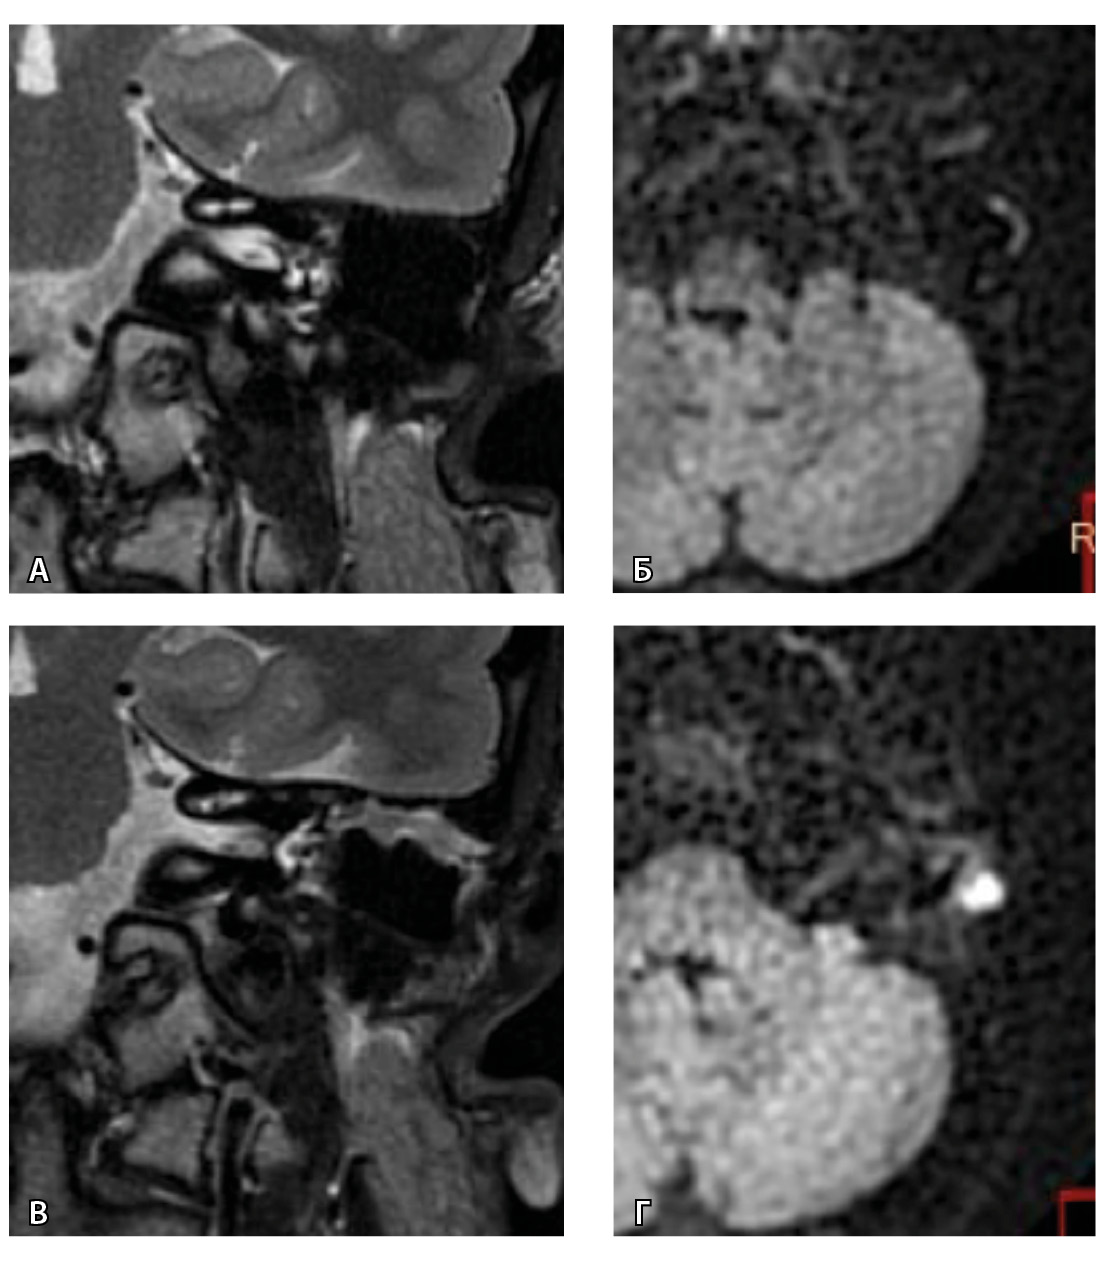

На рис. 3 и 4 показано расхождение данных КТ и МРТ.

Рис. 3. Хронический правосторонний средний отит. По данным компьютерной томографии (А, Б) нет ремоделирования барабанной полости, деструкции и смещения косточек, скутум сохранен, данных за холестеатому нет. При магнитно-резонансной томографии (В, Г) у того же пациента выявлен очаг высокого магнитно-резонансного сигнала, который при слиянии локализовался в области пространства Пруссака. Заключение и интраоперационно – холестеатома пространства Пруссака